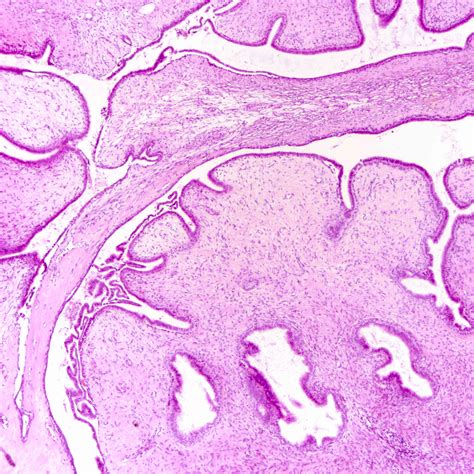

Benign phyllodes tumors are the most common type, accounting for approximately 60-70% of all phyllodes tumors. These tumors are typically slow-growing and have a low risk of recurrence. They are characterized by a well-defined border and a leaf-like architecture, with stromal overgrowth and epithelial components.

Histopathological analysis is the gold standard for diagnosing phyllodes tumors. A core needle biopsy or excisional biopsy is performed to obtain a tissue sample for microscopic examination. The histopathological features, including stromal overgrowth, epithelial components, and cellularity, are evaluated to determine the tumor's type and grade.